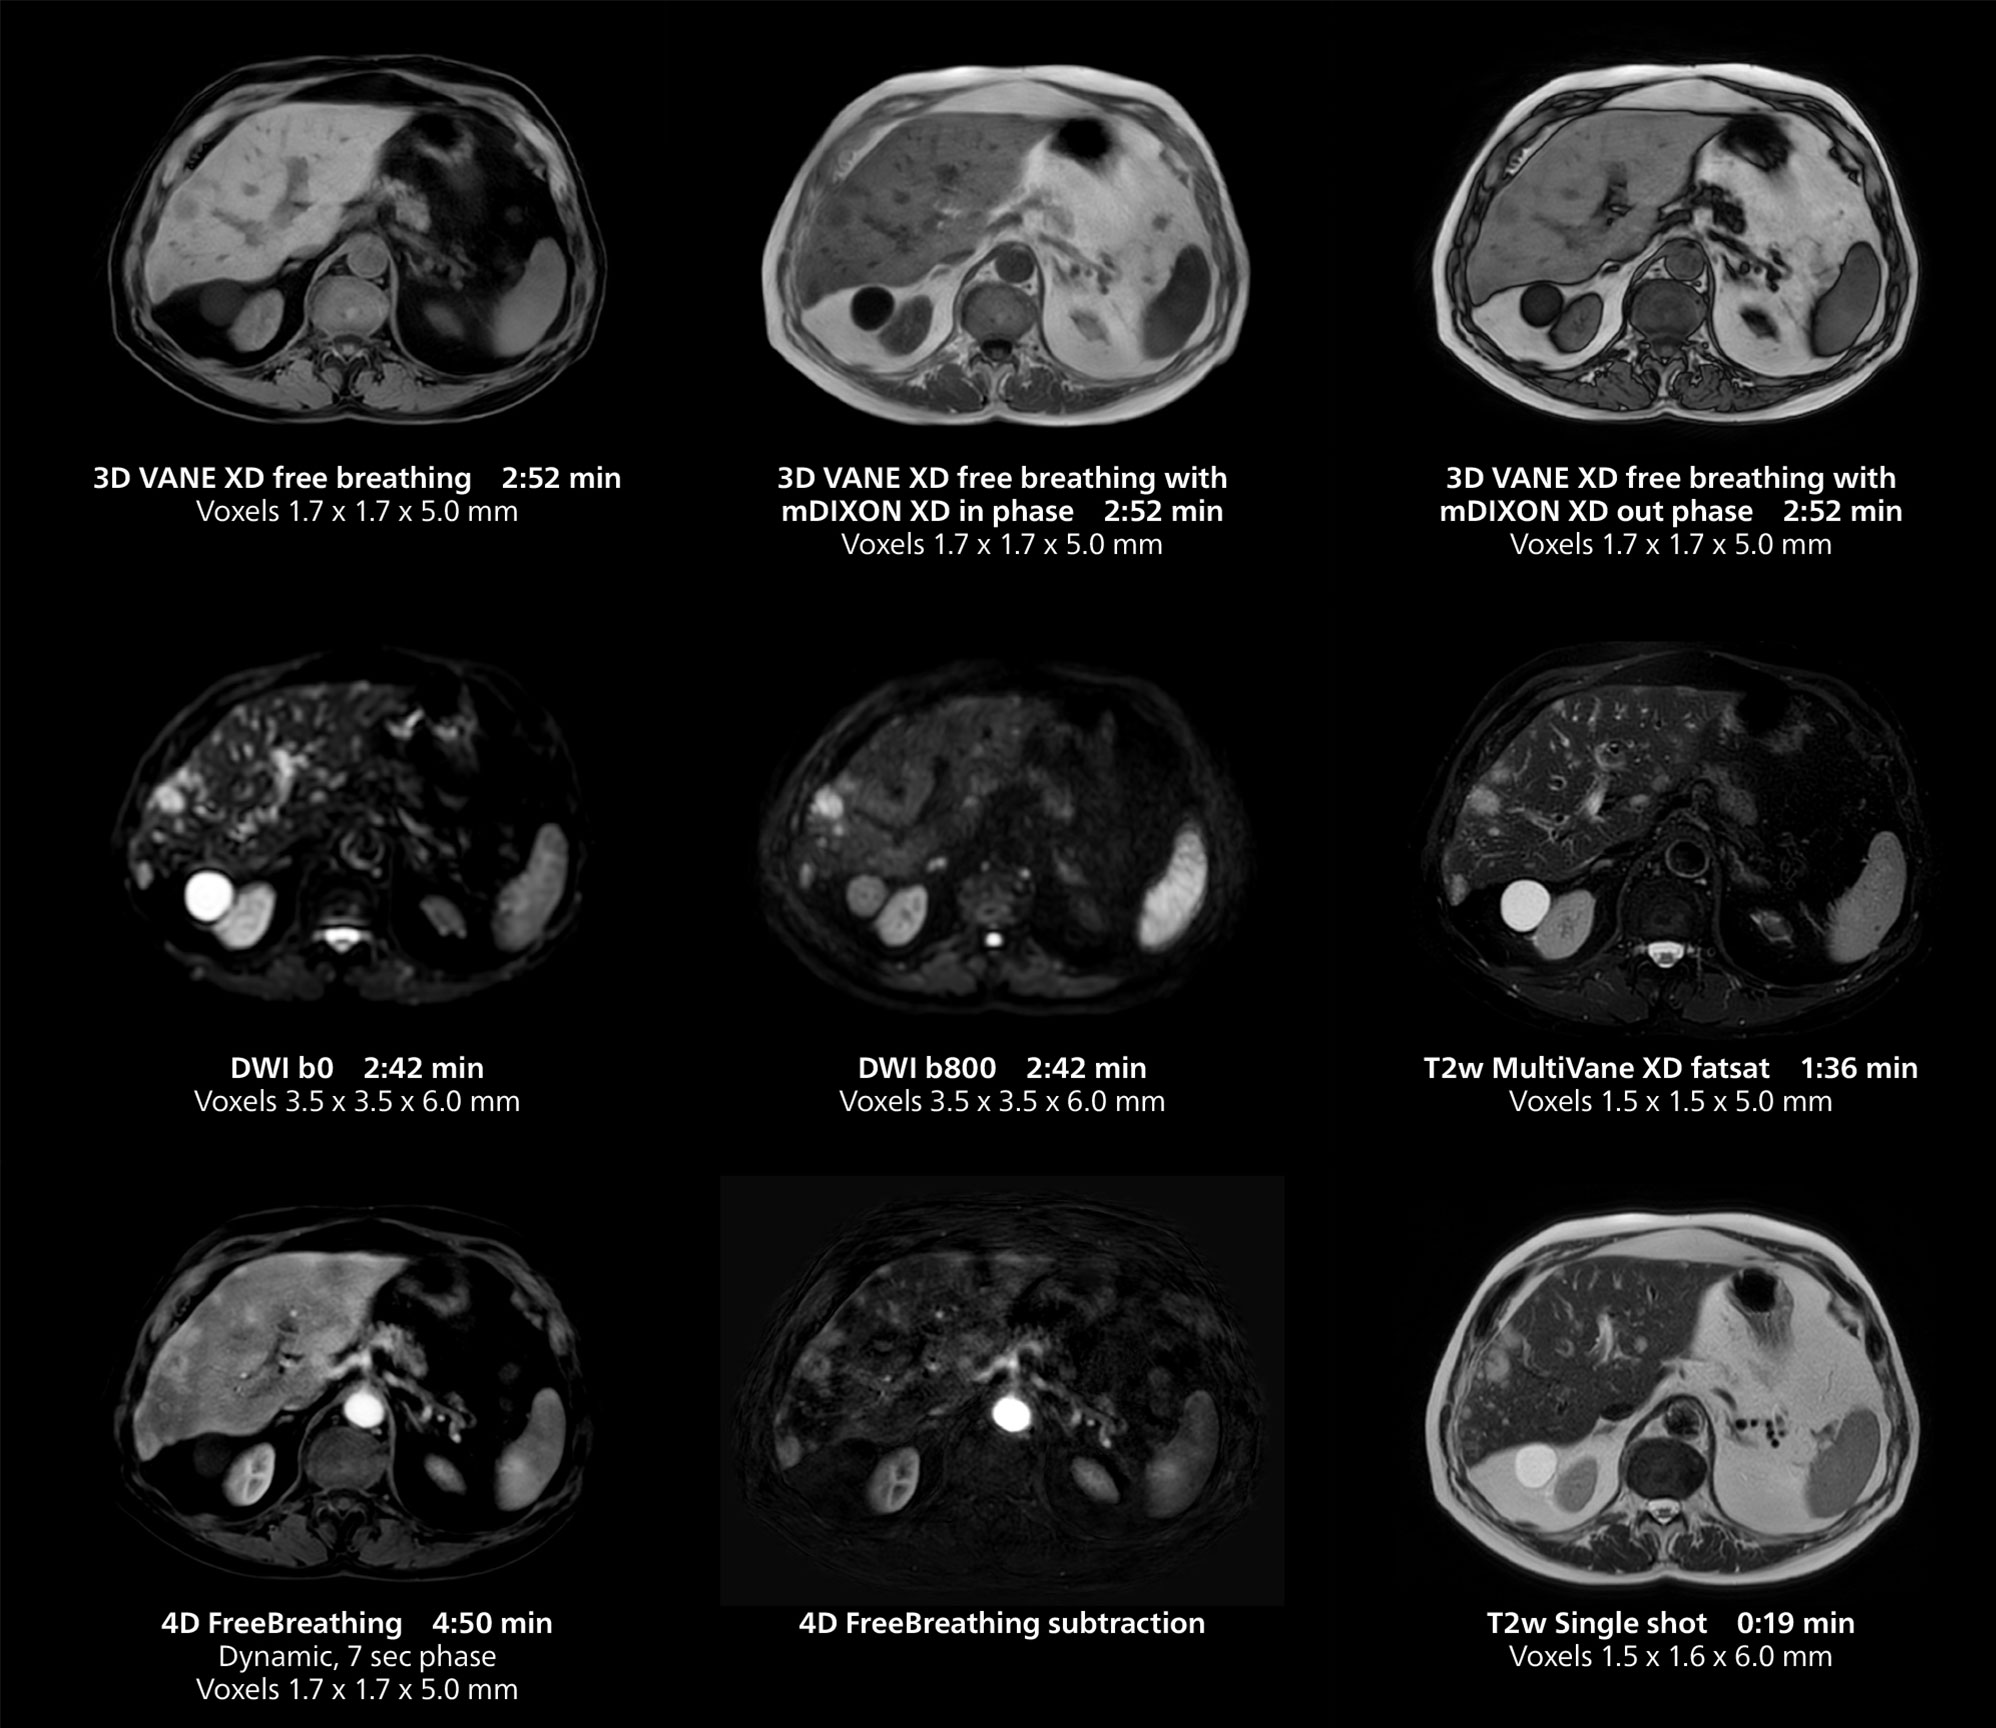

Liver imaging using MR 5300

This case includes 3D free breathing and 4D dynamic free breathing MRI of a metastasized liver. A high quality fatsat sequence with good resolution is obtained in 1:36 minutes with T2-weighted MultiVane XD.

Free-breathing scans provide reproducibility and patient comfort

Dr. Gellée highlights the robust free-breathing scans as “the feature that makes the biggest difference in my daily work. The 3D free breathing sequences are very reproducible, and the axial acquisition is very good. For example, in endometriosis, which is one of my focus areas, it provides high contrast and good resolution so that I can see small details. We also use free breathing for liver and pancreas imaging. In multi-phase liver studies, 4D Free Breathing delivers 3-second temporal resolution, making a dynamic scan with more than one arterial phase possible.”

She also uses free breathing with 3D mDIXON to obtain in-phase, water and fat images in a single scan. “It is very reproducible before and after gadolinium, which makes it useful for liver imaging,” she adds.